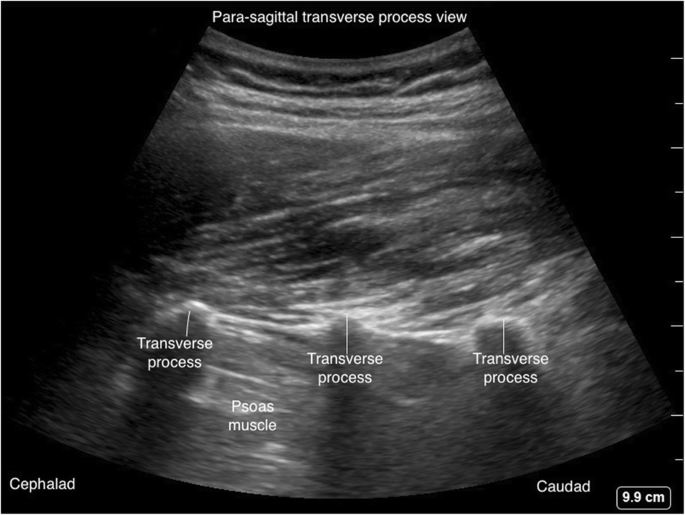

The para-sagittal windows can be obtained by beginning laterally with identification of ribs and pleura, then moving medially with identification of transverse process, articular process, and lamina. The para-sagittal interlaminar view (Figs. 21 and 22) is used to locate the interlaminar space as a marking point for the neuraxial procedure. The transverse views (Figs. 23 and 24) are challenging to obtain in the mid-thoracic spine as the transverse interspinous windows are narrow here. The presence of a rib marks the junction of the T12 and L1 vertebra. The 12th rib can be identified to locate the T12 vertebra, and the counting-down approach can be used to locate accurate lumbar intervertebral levels, or the counting-up approach can be used to locate the correct thoracic intervertebral level. Alternatively, the correct level can be determined by counting down from the T1 level, after locating the first rib.

파라사갈리탈 창은 늑골과 흉막을 식별하며 측방에서 시작하여, 가로 과정, 관절 과정, 및 층판을 식별하며 내측으로 이동하여 얻을 수 있습니다. 파라사갈리탈 간층판 관점(그림 21 및 22)은 신경축 수술의 표시점으로 간층판 공간을 위치시키는 데 사용됩니다. 횡단면(그림 23 및 24)은 흉추 중간 부위에서 횡간돌기 간 창이 좁기 때문에 획득이 어렵습니다. 늑골의 존재는 T12와 L1 척추체의 접합부를 표시합니다. 12번째 늑골을 식별하여 T12 척추를 위치시키고, 하향 계수 방법을 사용하여 정확한 요추 간 척추 수준을 찾거나, 상향 계수 방법을 사용하여 정확한 흉추 간 척추 수준을 찾을 수 있습니다. 또는 첫 번째 늑골을 위치시킨 후 T1 수준에서 하향 계수하여 정확한 수준을 결정할 수 있습니다.